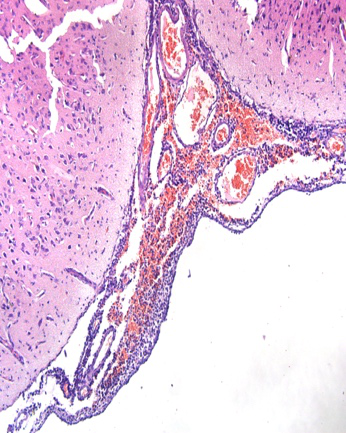

已经有足够的实验室数据和临床案例证明蓝耳病和一些细菌性疾病有非常紧密的相关性。蓝耳病毒会在肺血管巨噬细胞和肺泡巨噬细胞内复制并将其杀死。与人和啮齿类动物不同的是(人和啮齿类动物清除血液中的细菌和颗粒主要有肝脏枯否也细胞和脾脏巨噬细胞来完成),猪清除血液循环中的颗粒、细菌、内毒素的细胞主要是肺相关巨噬细胞。肺内巨噬细胞群损伤会会极大的降低其吞噬作用和杀菌作用。猪单纯感染蓝耳病毒机体可能是可以耐过的,蓝耳会继发很多条件性致病菌,包括链球菌,副猪嗜血杆菌,猪嗜血杆菌等,并且很多情况下保育猪会死于这种激发性的细菌性疾病。感染蓝耳病的个体结局可能有多种,或者死于间质性肺炎导致的呼吸系统的衰竭,病毒型肺炎引起的间质性肺炎会严重的降低肺的气体交换能力,机体无法得到足够的氧气衰竭而死,在病毒感染压力巨大的猪场,蓝耳个体多死于这种情况。还有一种情况是继发的细菌性疾病如链球菌和副猪嗜血杆菌引起的浆膜炎和脑膜炎,其中包括心包炎,胸膜炎,腹膜炎等。浆膜炎属于慢性消耗性疾病,个体猪最后会多系统衰竭而死。最后一种是面对同样环境,同样毒株存活的猪。

浆膜炎可以作为衡量蓝耳感染压力的另一个指标,浆膜炎会累及实质器官,使器官功能障碍,在蓝耳感染压力很大的猪场,很容易见到这种情况

不过浆膜炎属于细菌性疾病范畴,通常不会由病毒直接引起

图片来源于蓝耳不稳定场